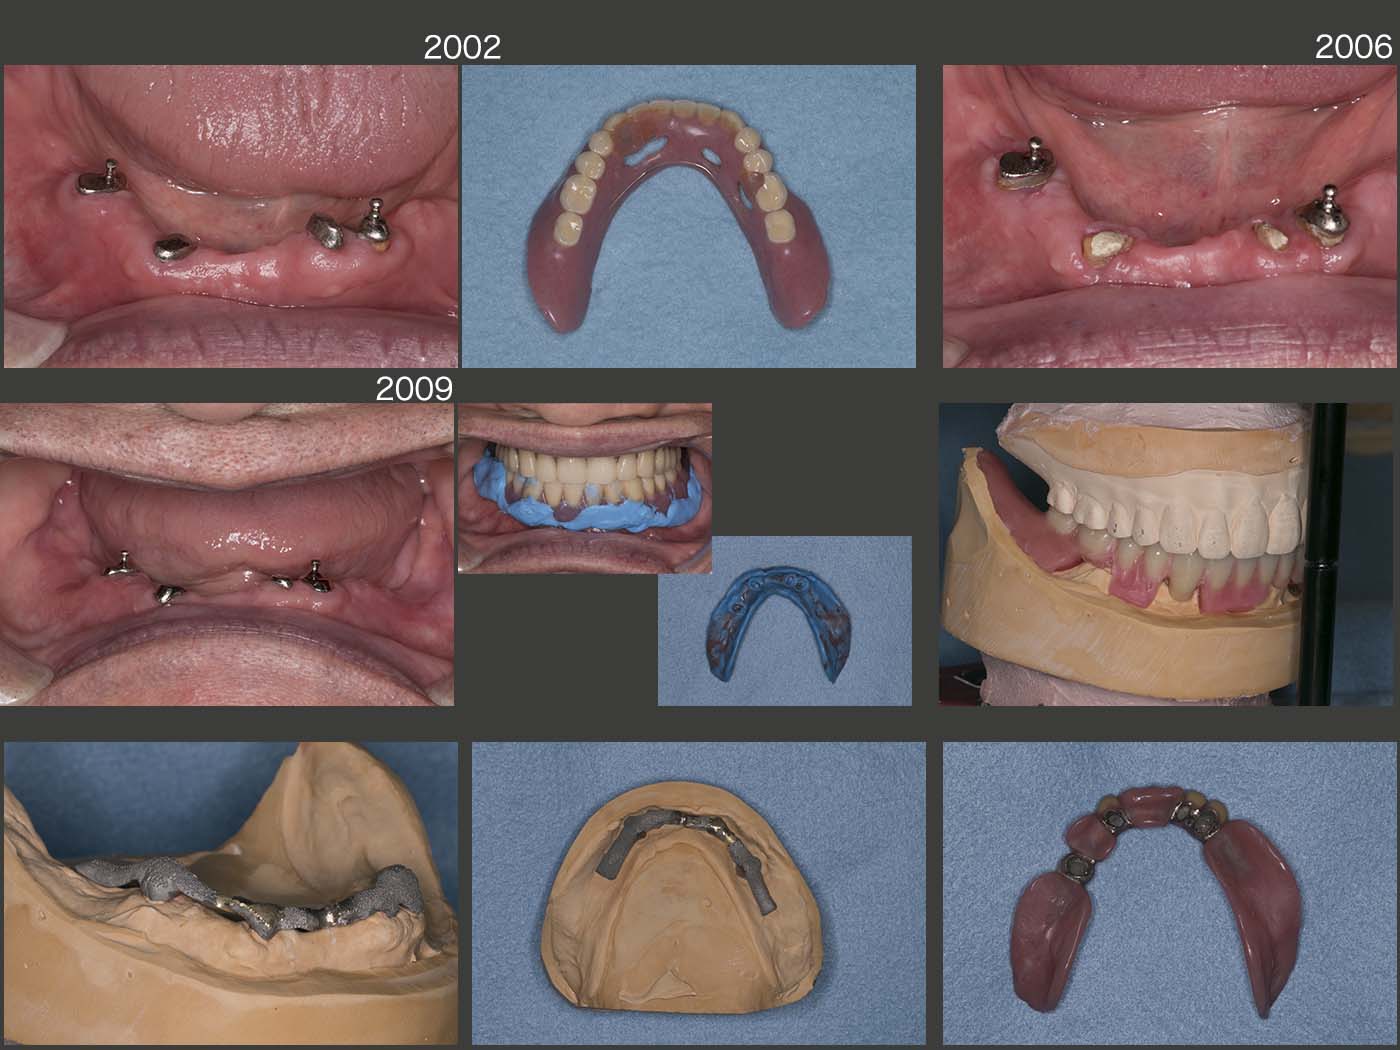

2016年11月初診,68歳男性.当院,代診の先生の症例.保存可能な左下3,右下5にOPAアタッチメントを,左下2,右下3に根面板を製作し,17年2月に上下顎に総義歯を装着した.この時の下顎義歯は,支台歯辺縁歯肉を義歯床で覆う形態であった.

スライドに掲載していないが,2018年3月,根面カリエスにて右下5のアタッチメントを作り直した.他の残存歯にも根面カリエスが認められた.患者さんは,よく飴を舐めていたとのことで,可能な限りやめて頂くようにお願いし,経過を観察することした.

20年2月のリコール時,残念ながらう蝕が進行し,これ以上の放置は危険であることから再治療を行うことになった.今回は,積極的に支台歯辺縁歯肉の開放を行いたい旨を説明し,同意して頂いた.まず,旧義歯を改変し,特に舌側の開放部に異物感が生じるか否かの反応を確認した.つぎに6月,左右側に分けて歯冠長延長術を行い,歯肉縁上歯質の確保を行った.9月,OPAアタッチメントおよび根面板を再製作した.旧義歯を用いての咬合圧印象を行うことで咬合採得も同時に行った.デンチャースペースが十分とれるため,上部構造体は義歯床に埋め込む形態とした.